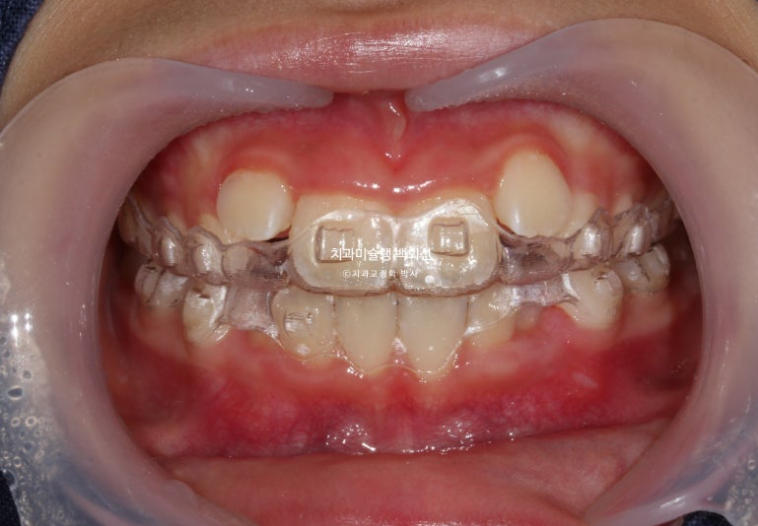

파란화살표 부분을 보자면

장치 양옆에 날개처럼 튀어나온 부분이 Wing 이며 이 부분이 아래턱의 위치를 정상위로 유도합니다.

23.11

사진의 파란화살표처럼 위 아래 윙 끼리 엇갈려 물리며 아래턱을 전방위치 시키며, 최대성장기와 맞물리면 하악골 성장까지 유도하게 됩니다.